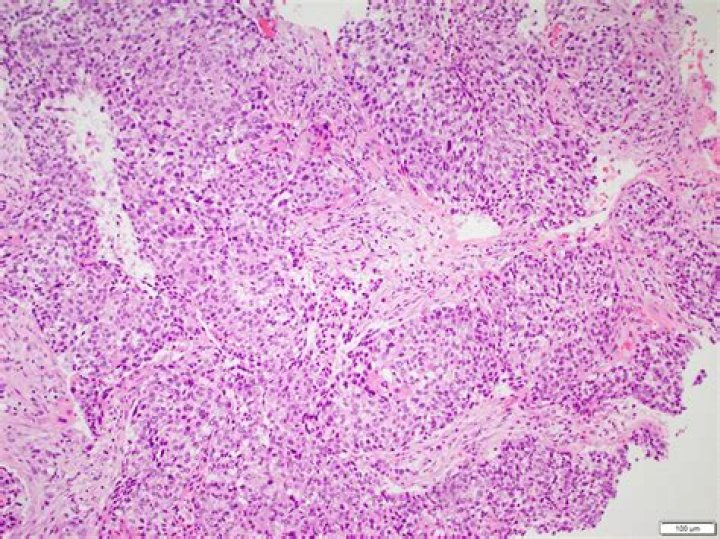

What is Basaloid squamous cell carcinoma?

Basaloid squamous cell carcinoma (Bas-SqCC) is an uncommon histological variant of lung cancer composed of cells exhibiting cytological and tissue architectural features of both squamous cell lung carcinoma and basal cell carcinoma.